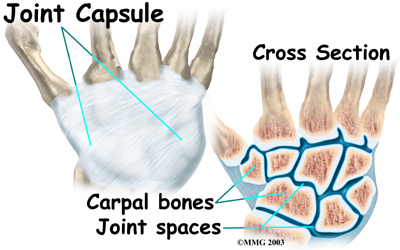

One reason that the wrist is so complicated is because every small carpal bone forms a joint with the bone next to it. This means that what we call the wrist joint is actually made up of many small joints.

A joint capsule is a watertight sac that surrounds a joint and contains lubricating fluid called synovial fluid. In the wrist, the eight carpal bones are surrounded and supported by a joint capsule.